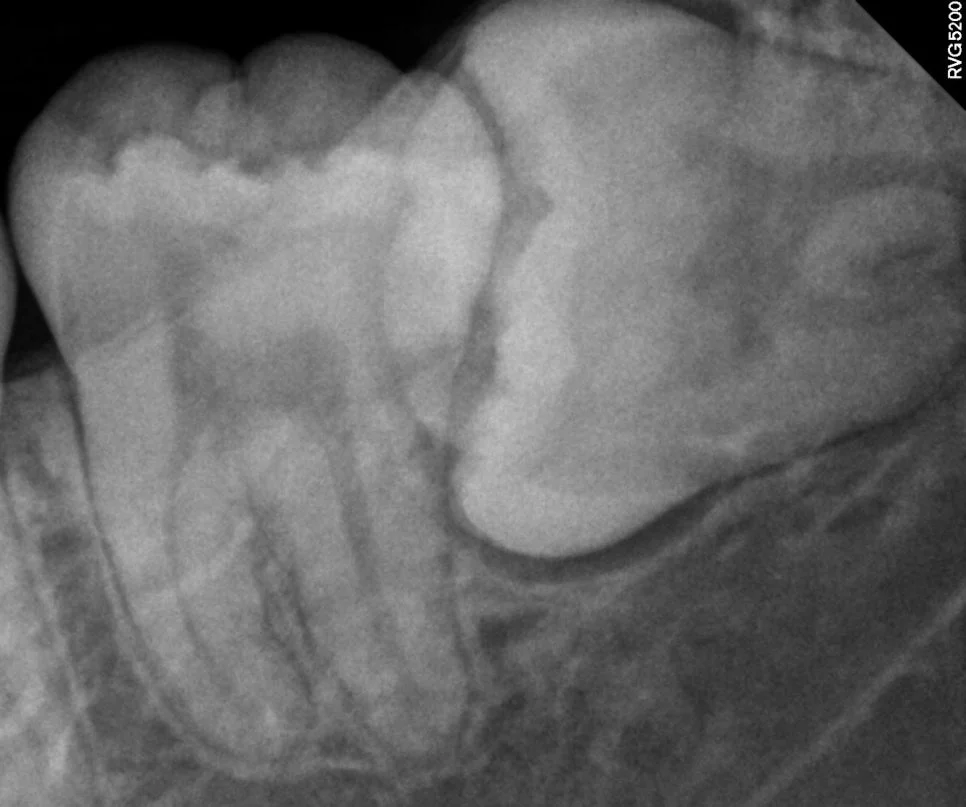

우측 매복 사랑니 진단

매복 사랑니 우측 치근단 X-ray 수평 매복

우측 치근단 X-ray (수평 매복)

제2대구치를 위협하는 우측 하악 매복 사랑니입니다. 잇몸 아래에 완전히 매복되어 있는 상태를 확인할 수 있습니다.